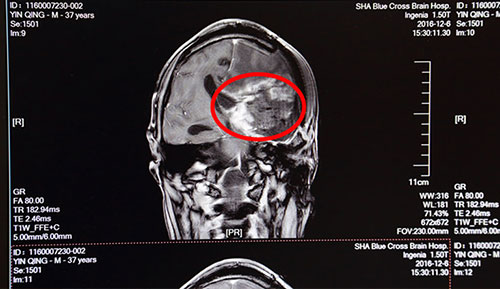

術(shù)前影像資料:紅圈內(nèi)為腫瘤物

藍(lán)十字腦科醫(yī)院神經(jīng)外科侯增欣主任等針對患者病情進(jìn)行了聯(lián)合會診討論。根據(jù)患者病史及影像學(xué)資料,腫物位于左側(cè)額顳葉,占位效應(yīng)及高顱壓癥狀明顯;颊吣壳熬哂惺中g(shù)指征,需盡早手術(shù)治療,術(shù)中應(yīng)盡量切除腫瘤,緩解顱內(nèi)壓,明確診斷,否則恐危及生命。又鑒于患者多次手術(shù),且腫瘤血供豐富,術(shù)中可能大出血,術(shù)后可能出現(xiàn)肢體癱瘓加重且永久、偏身感覺障礙及顱內(nèi)遲發(fā)性出血、血腫或其他部位出血(如腦室內(nèi)出血)等,危及生命可能。此外,患者此前做過粒子植入術(shù),粒子為高放射物,相關(guān)機(jī)構(gòu)對粒子的管控極其嚴(yán)格,不僅需要申請資質(zhì),而且每一枚粒子的出入都經(jīng)過嚴(yán)格備案,一般醫(yī)院是沒有粒子相關(guān)處理經(jīng)驗(yàn)的,因此對手術(shù)如何處理病人顱腦中植入的粒子也是極其棘手的問題。由此可見手術(shù)難度之大,將十分考驗(yàn)主刀醫(yī)生,實(shí)為不小的挑戰(zhàn)。